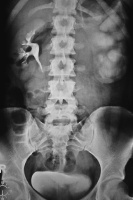

Harnwegsinfekte: Was macht der Urologe und wann sollte er eingeschaltet werden?

Journal für Urologie und Urogynäkologie 2011; 18 (1) (Ausgabe für Schweiz): 32-34 Journal für Urologie und Urogynäkologie 2011; 18 (1) (Ausgabe für Österreich): 31-32 Volltext (PDF) Abbildungen